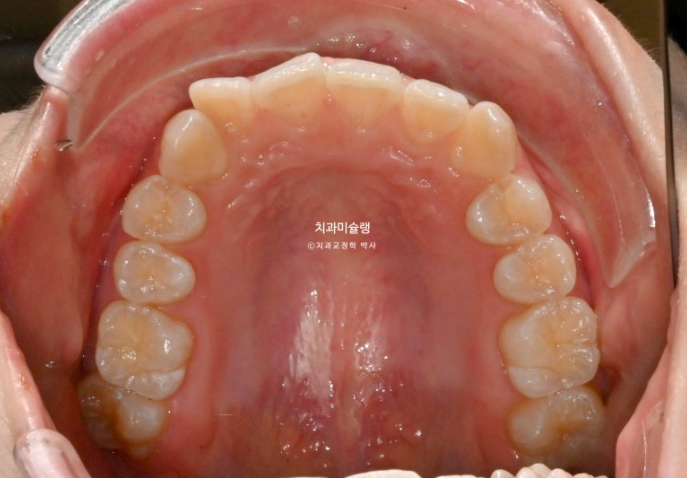

윗니 정중앙 블랙트라이앵글은 치간삭제를 통해 줄였으며

중심선은 처음에 비해 많이 개선되었습니다.

중심선 불일치가 미세하게 남았지만 만족스럽게 개선되었으며

어금니 교합은 좋습니다.